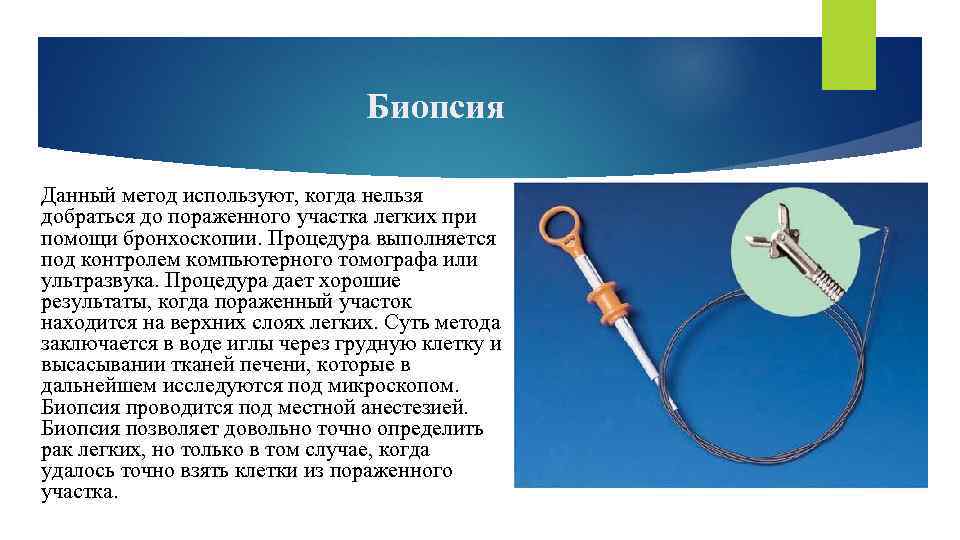

Биопсия Данный метод используют, когда нельзя добраться до пораженного участка легких при помощи бронхоскопии. Процедура выполняется под контролем компьютерного томографа или ультразвука. Процедура дает хорошие результаты, когда пораженный участок находится на верхних слоях легких. Суть метода заключается в воде иглы через грудную клетку и высасывании тканей печени, которые в дальнейшем исследуются под микроскопом. Биопсия проводится под местной анестезией. Биопсия позволяет довольно точно определить рак легких, но только в том случае, когда удалось точно взять клетки из пораженного участка.

Биопсия Данный метод используют, когда нельзя добраться до пораженного участка легких при помощи бронхоскопии. Процедура выполняется под контролем компьютерного томографа или ультразвука. Процедура дает хорошие результаты, когда пораженный участок находится на верхних слоях легких. Суть метода заключается в воде иглы через грудную клетку и высасывании тканей печени, которые в дальнейшем исследуются под микроскопом. Биопсия проводится под местной анестезией. Биопсия позволяет довольно точно определить рак легких, но только в том случае, когда удалось точно взять клетки из пораженного участка.